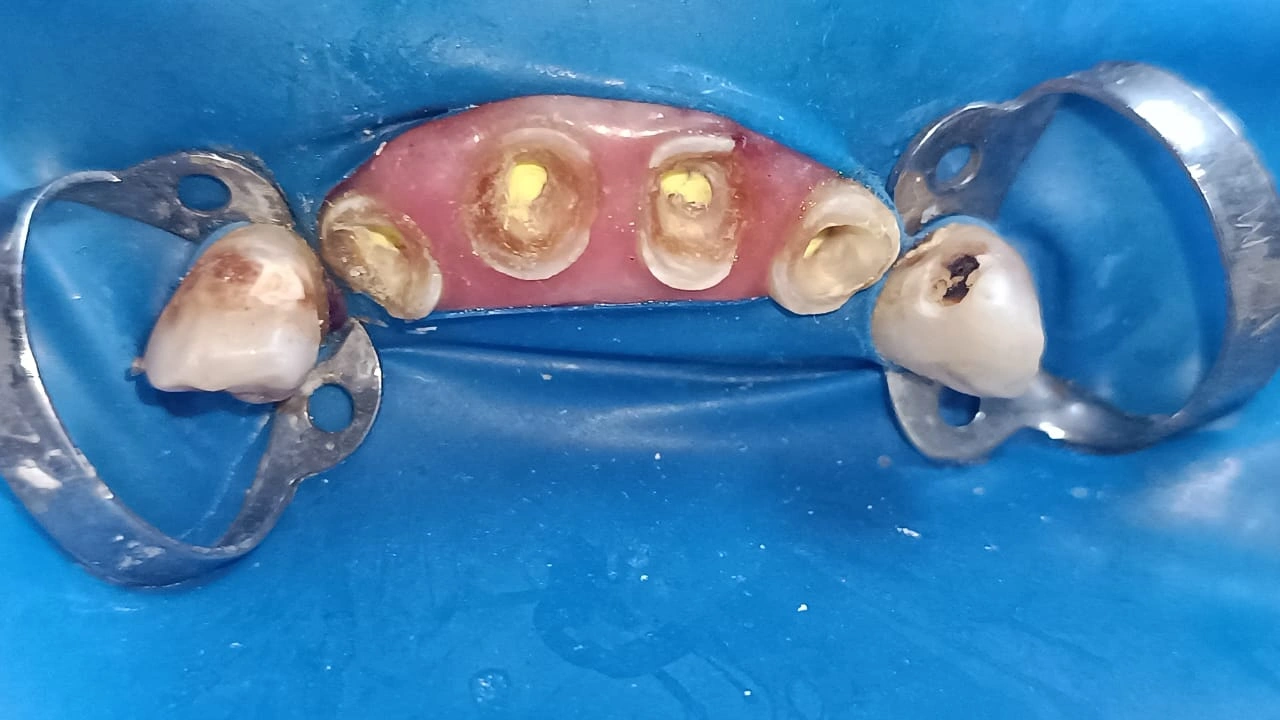

Selective caries removal stage

RCT for 4 anteriors